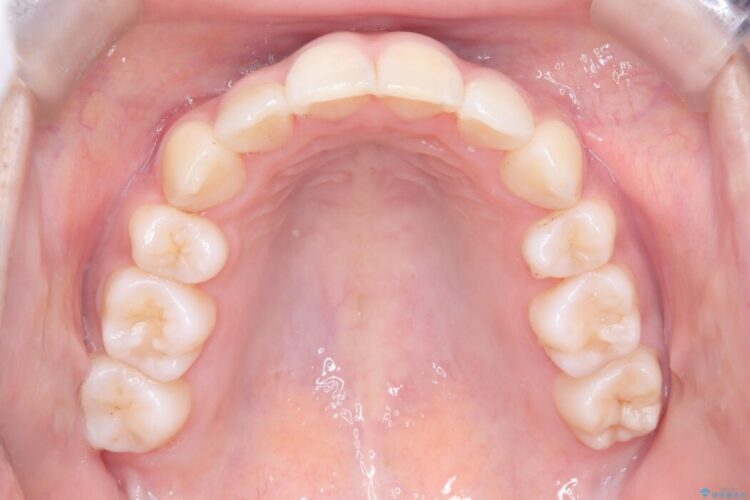

矯正検査の結果、歯を並べるスペースが不足しており、そのまま並べてしまうとさらに突出感が目立つ恐れがありました。

そのため上下左右4番を抜歯し、ガタつきを改善しながら前歯をしっかりと後方へ下げ、口元のボリュームを抑えていく計画を立案しました。

複雑に重なり合っていた前歯を、抜歯で作ったスペースを活用して丁寧に整列。単に並べるだけでなく、角度を1ミリ単位で調整しながら後ろへ下げることで、口元の突出感をスッキリ解消しました。